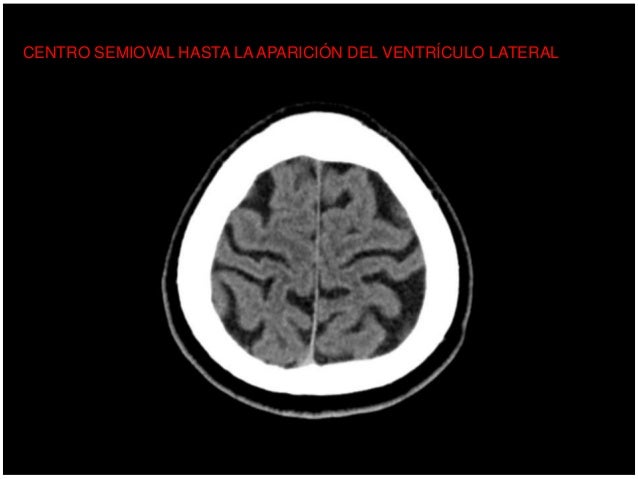

Lectura Sistematica Del Tc De Craneo